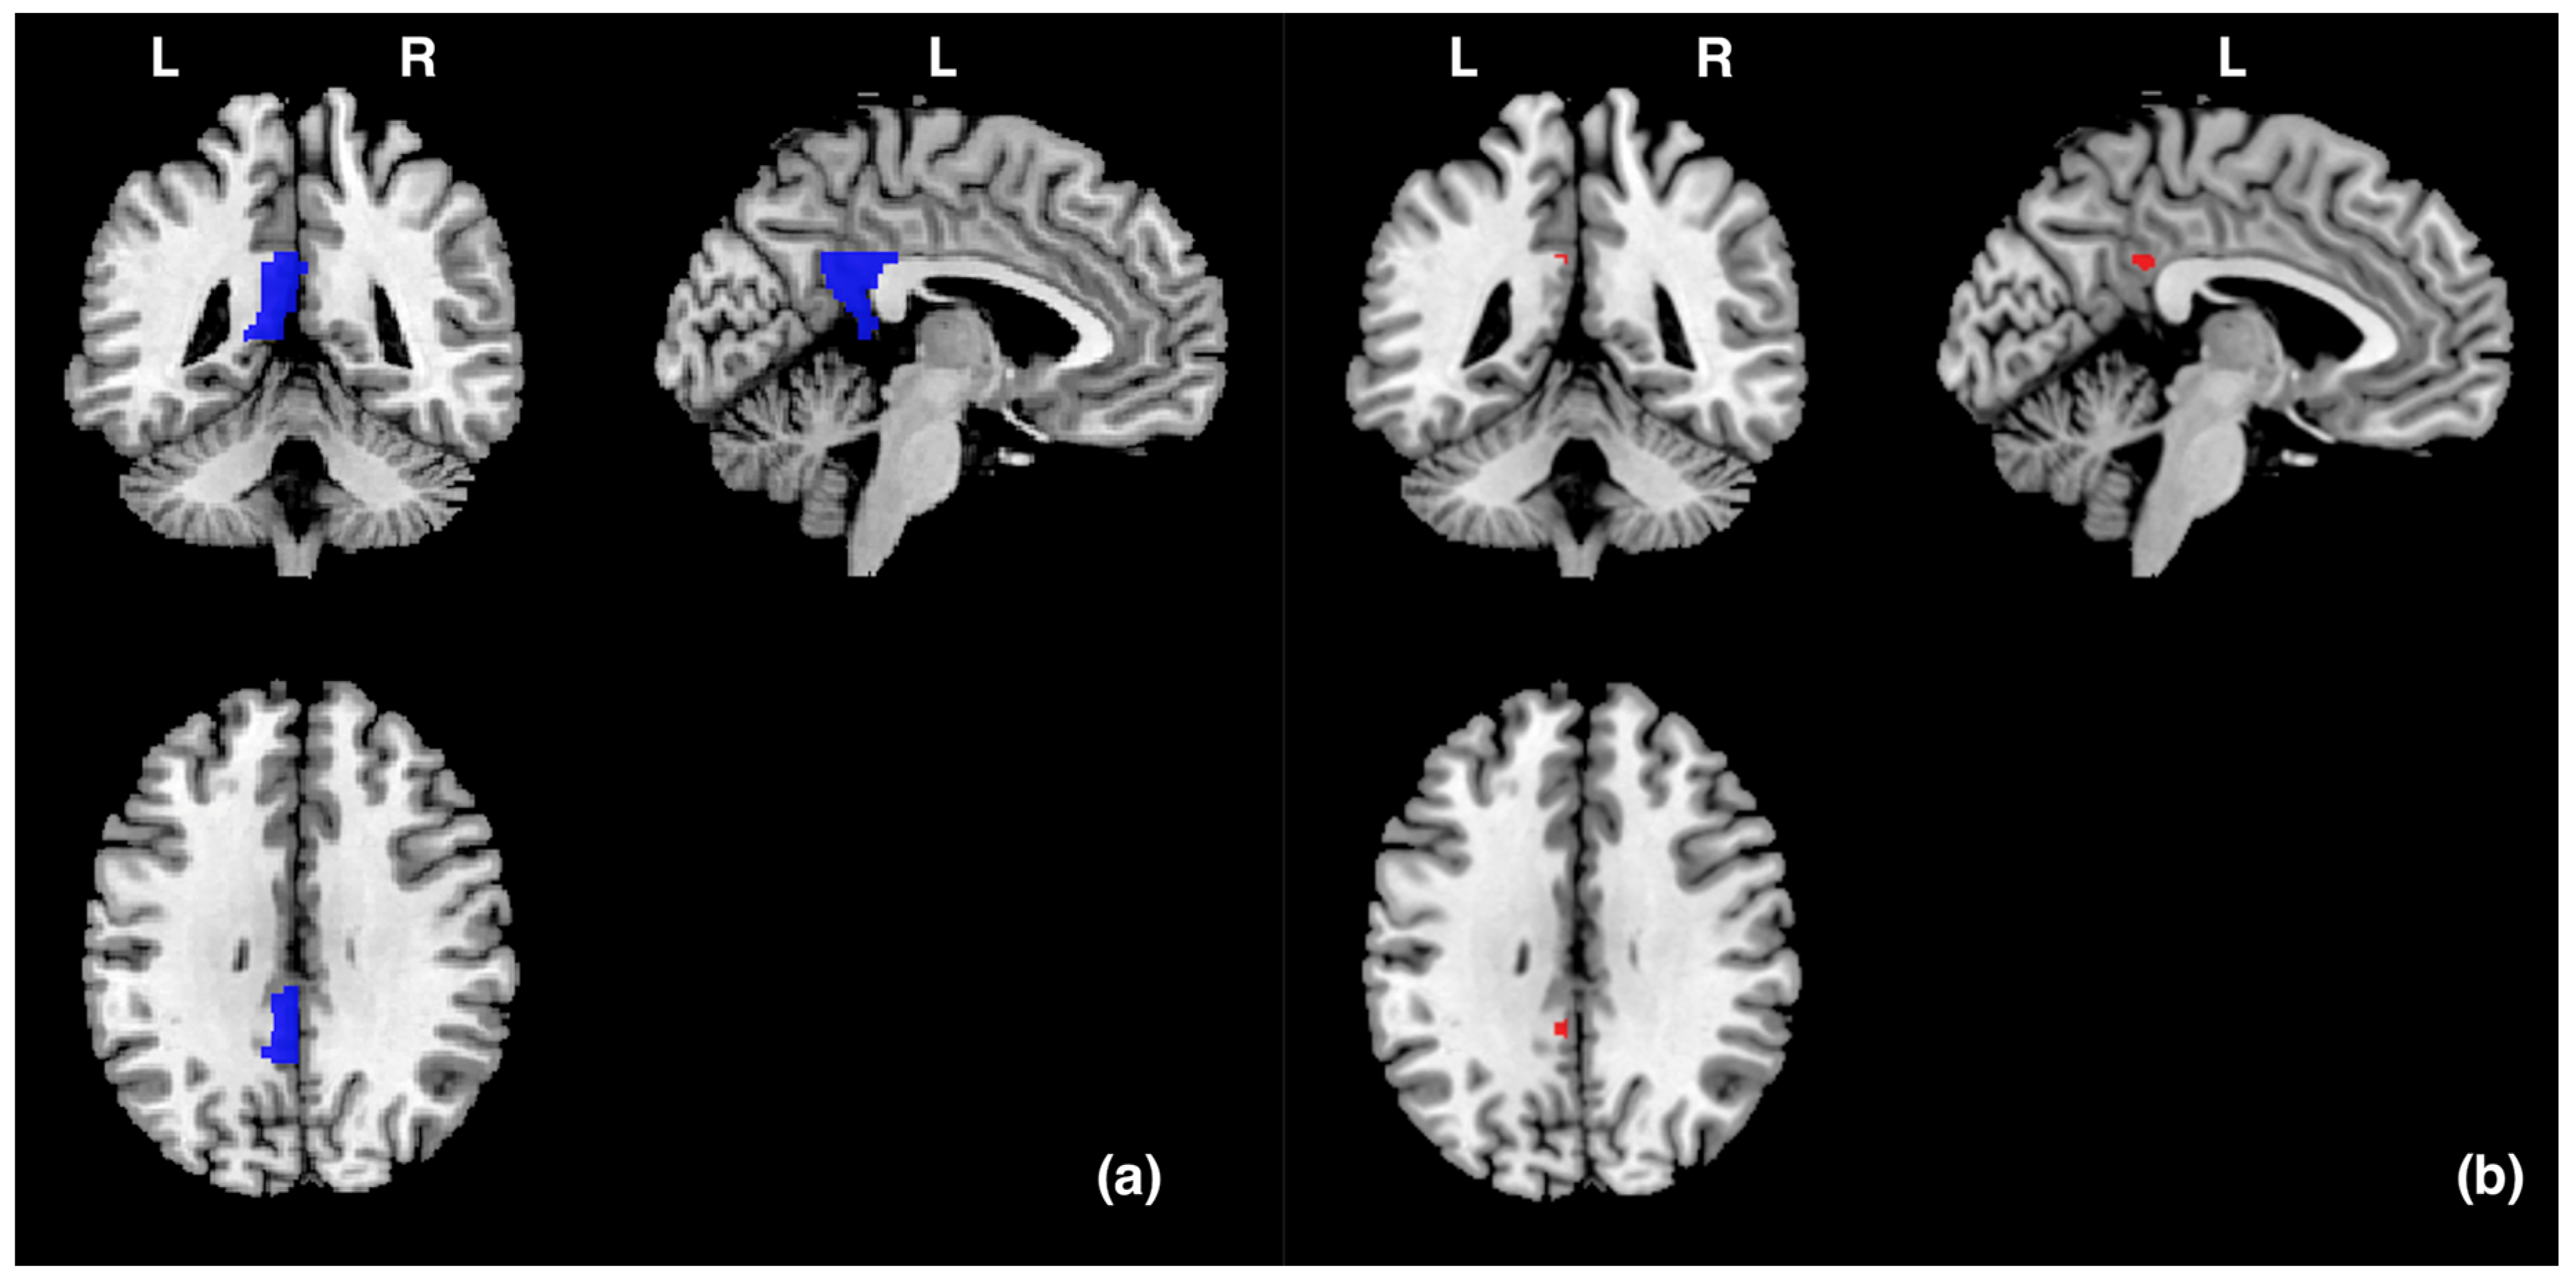

3.1. Brain Activity in Left Posterior Cingulate Gyrus

| Brain Area Brodman Area (BA) | Number of Voxels in Cluster | Voxel−Level p Value FWE−Corrected | Voxel−Level p Value Uncorrected | T Value at Local Maximum | MNI Coordinates | ||

|---|---|---|---|---|---|---|---|

| x | y | z | |||||

| Posterior Cingulate Gyrus (BA31) | 4 | 0.016 | 0 | 4.71 | −4 | −44 | 32 |